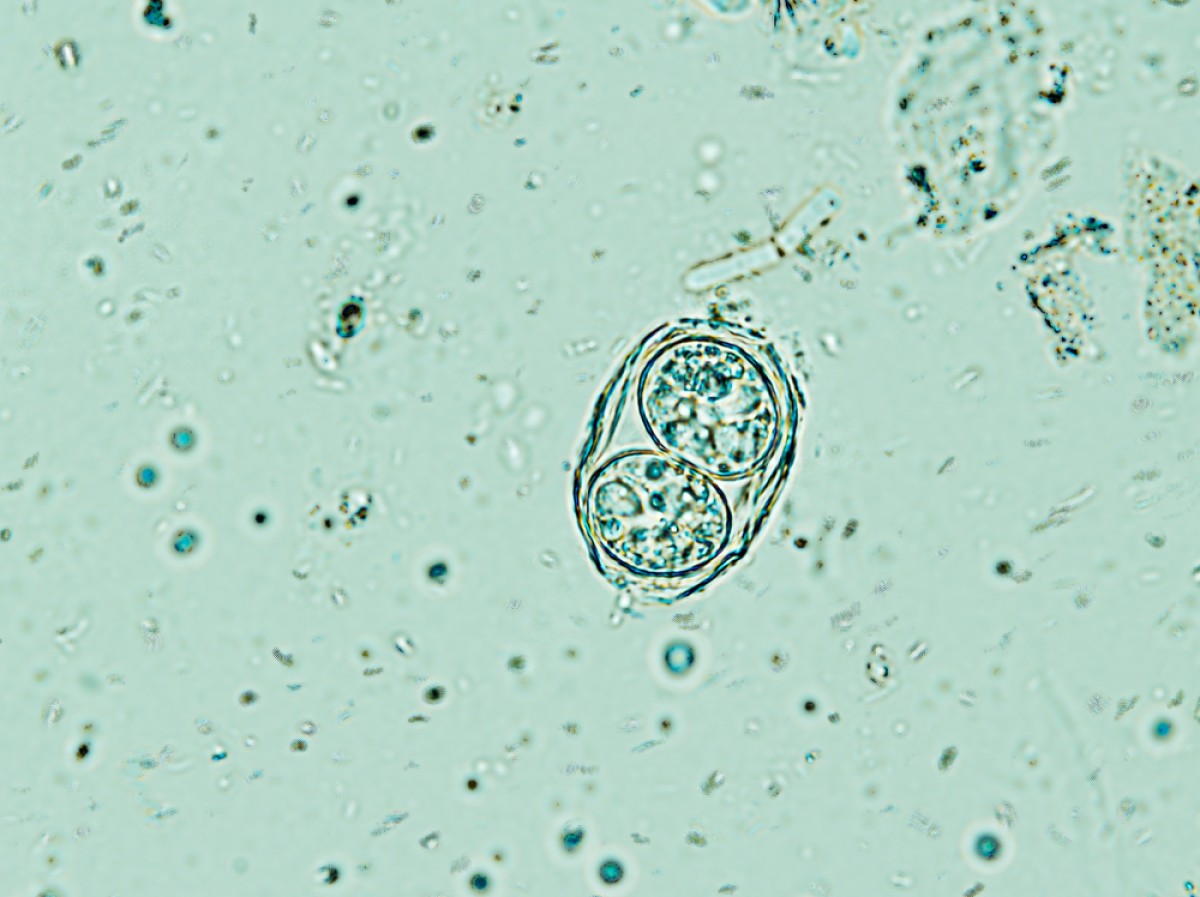

Anticorps anti-Toxoplasma gondii chez les résidents européens : revue systématique et méta-analyse des études publiées entre 2000 et 2020

La toxoplasmose entraîne d’importantes conséquences sur la santé publique et animale. À ce jour, les informations concernant la séroprévalence des infestations par Toxoplasma gondii chez l’homme à l’échelle de l’Europe n’ont pas encore été compilées. L’objectif de la présente étude était par conséquent de résumer les données disponibles sur les résidents entre 2000 et 2020. La séroprévalence globale des IgG anti-T. gondii a été de 32,1 %, avec une grande variabilité entre les pays (n = 30). L’analyse des sous-groupes a permis de distinguer les données de prévalence groupées en fonction de la zone géographique (p < 0,0001), de la population cible (p = 0,0147) et des sérodiagnostics utilisés (p = 0,0059). Une grande hétérogénéité (indice I2 = 100 %, p < 0,001 ; test Q de Cochrane = 3,5e+05, degré de liberté [d.f.] = 135, p < 0,001) et un degré élevé de biais de publication (test d’Egger = 6,14, p < 0.001) ont été observés parmi les 134 études prises en compte. La présence d’IgM anti-T. gondii, signalée dans 64,7 % des études, a atteint une séroprévalence groupée de 0,6 %.

En outre, parmi les huit principaux facteurs de risque identifiés, le « contact avec le sol », la « consommation de viande de bœuf insuffisamment cuite » et la « consommation de légumes non lavés » ont été les plus significativement associés aux infestations. Le fait qu’un tiers de la population européenne a été exposé à T. gondii justifie de réaliser des efforts supplémentaires pour harmoniser les systèmes de surveillance et développer des analyses supplémentaires des facteurs de risque basées sur une évaluation détaillée de la détermination de la source.